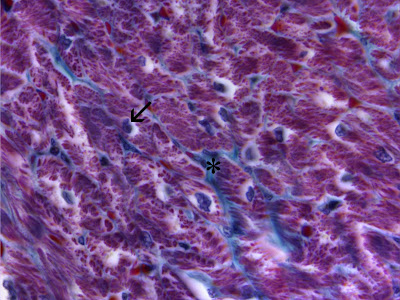

| Órgão: Coração

Descrição: Tecido muscular estriado cardíaco. Em corte transversal, nas células cardíacas nota-se uma região clara e perinuclear, a qual corresponde ao local de glicogênio no citoplasma da célula (→). Tecido conjuntivo frouxo (*).